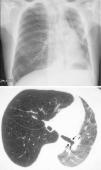

However, BOS is not the only manifestation of chronic rejection. Patterns other than obstruction that are not included under BOS have been described. Chronic lung allograft dysfunction (CLAD) is probably a better way of defining a chronic decline in FEV1 than BOS. In recent years, it has been observed that CLAD is a heterogeneous condition defining different phenotypes, including, in addition to the classic BOS, other patterns that include partial reversibility to airway obstruction, restrictive ventilatory deterioration and changes in lung parenchyma.22 Neutrophilic reversible allograft dysfunction (NRAD) is characterised by airway neutrophilia (bronchoalveolar lavage [BAL]>15% neutrophils) and functional improvement (>10% in FEV1) after azithromycin treatment.23–26 Restrictive allograft syndrome (RAS) comprises 25%–35% of CLAD and is defined as a fall from baseline in total lung capacity (TLC) greater than 10% and fibrosis, predominantly in the upper lobes (Fig. 4). It progresses more rapidly and has a poorer prognosis than BOS.27,28

Pulmonary fibrosis changes in upper lobes of a patient diagnosed with restrictive allograft syndrome (chest X-ray and chest CT).